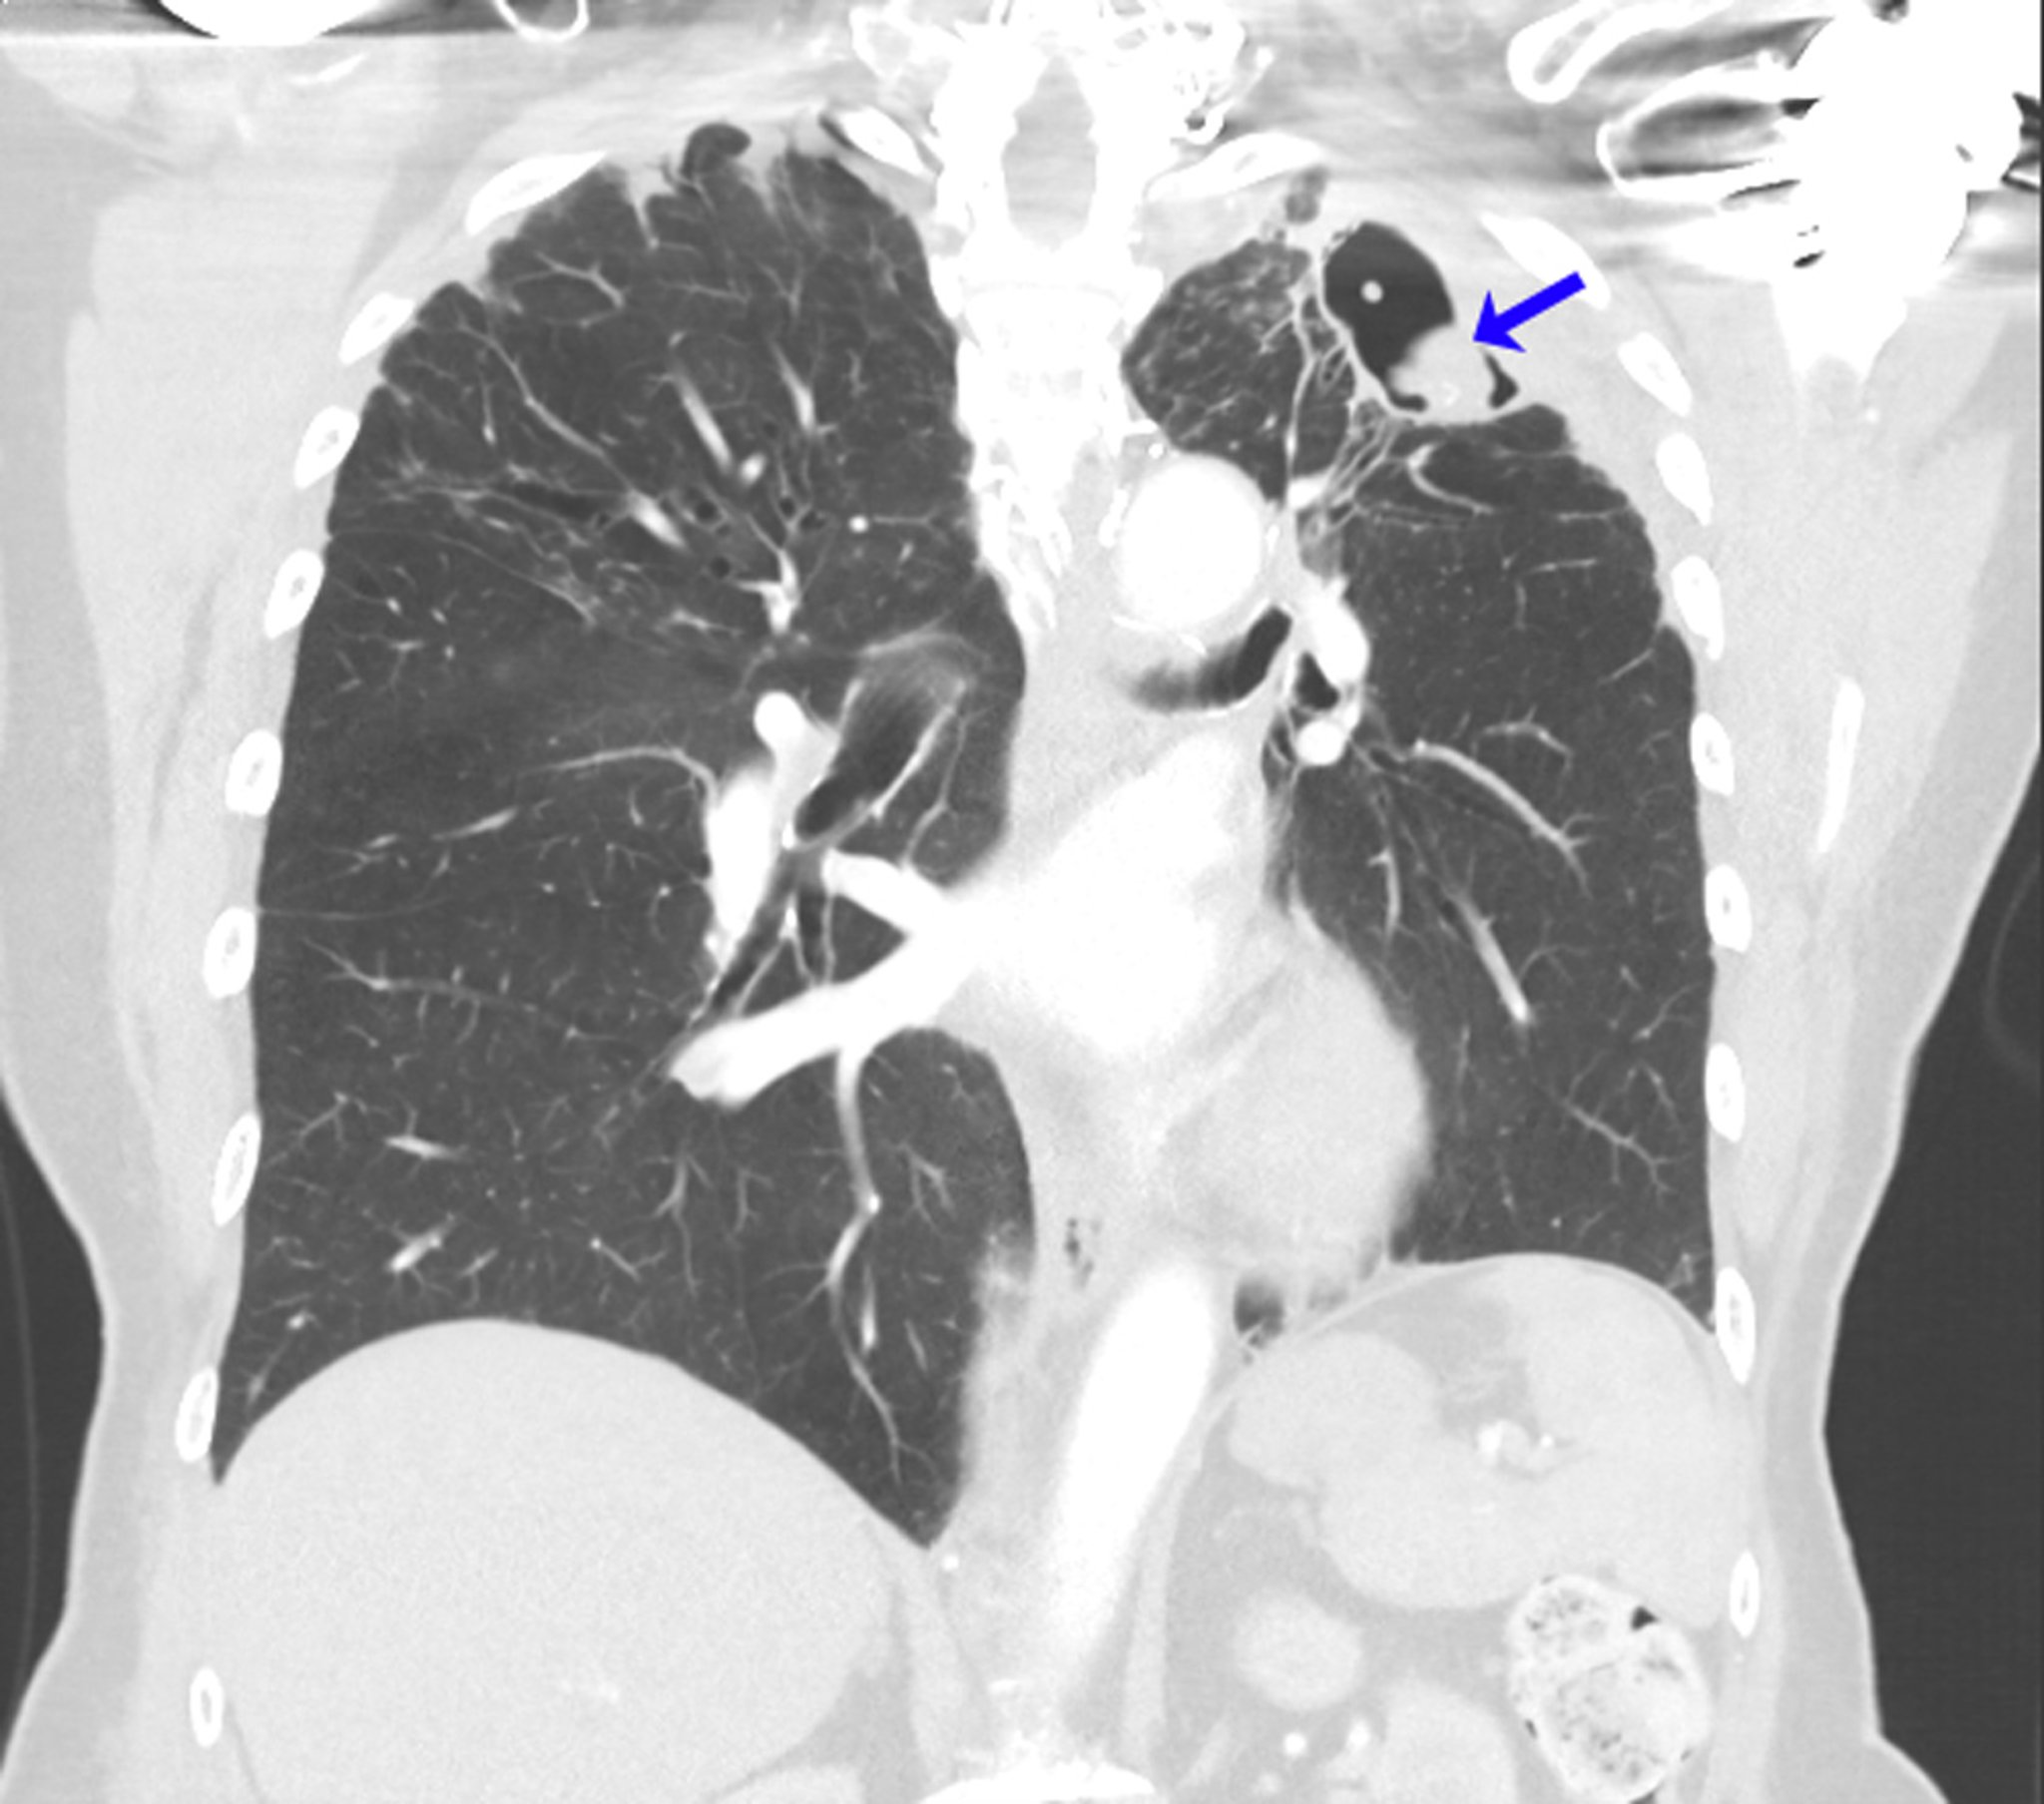

Рецидивирующая аспергиллома

На данной компьютерной томограмме показаны легкие человека с аллергическим бронхолегочным аспергиллезом в анамнезе на фоне бронхиальной астмы. На верхушке левого легкого развился рецидив мицетомы (стрелка) после левосторонней лобэктомии по поводу аспергилломы.

Image courtesy of Paschalis Vergidis, MD, MSc.